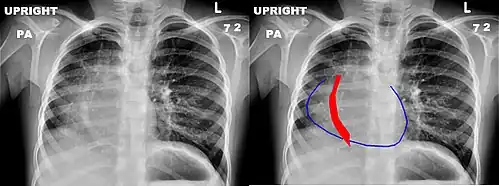

Scimitar syndrome, or congenital pulmonary venolobar syndrome, is a rare congenital heart defect characterized by anomalous venous return from the right lung (to the systemic venous drainage, rather than directly to the left atrium).[1] This anomalous pulmonary venous return can be either partial (PAPVR) or total (TAPVR). The syndrome associated with PAPVR is more commonly known as Scimitar syndrome after the curvilinear pattern created on a chest radiograph by the pulmonary veins that drain to the inferior vena cava.[2] This radiographic density often has the shape of a scimitar, a type of curved sword.[2] The syndrome was first described by Catherine Neill in 1960.[3]

The anomalous venous return forms a curved shadow on chest x-ray such that it resembles a scimitar. This is called the Scimitar Sign. Associated abnormalities include right lung hypoplasia with associated dextroposition of the heart, pulmonary artery hypoplasia and pulmonary sequestration. Incidence is around 1 per 100,000 births.[4]

Chest x-ray of a five-year-old girl with Scimitar syndrome. The heart (blue outline) is shifted into the right half of the chest, and the anomalous pulmonary venous return (red) has a shape reminiscent of a Scimitar.